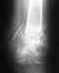

Re: Несрастающийся чрезвертельный перелом

Сейчас конструкция несостоятельная. Надо в любом случае ее удалять и заменять на другую, чтобы обеспечить немедленную возможность ходьбы с нагрузкой без риска смещения. Времени на лечение уже ушло в несколько раз больше обычного.

У нас в отделении сейчас делается довольно много операций по такого рода поводам. Предпочли бы сделать остеосинтез стержнем. Есть модификации, исключающие миграцию, подобную случившейся. Делать какие-то пластики и вообще широко обнажать кость не видно необходимости. Возможно, будет целесообразно увеличить шеечно-диафизарный угол.

Технических вариантов несколько, для выбора конкретного варианта надо посмотреть и очно, и предшествующие снимки, и сделать снимок таза с обоими тазобедренными суставами.